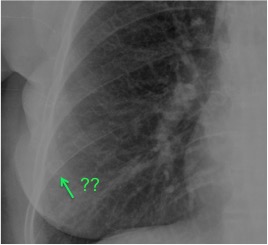

CASO: Febrícula y tos de 4 días de evolución.

Hallazgos:

- En la placa PA se observa una asimetría en los hilios pulmonares, el hilio izquierdo tiene una densidad aumentada.

- Tras examinar la placa lateral se observa un aumento de densidad en la columna que puede ser compatible con una condensación, es el signo de la desnificación vertebral.

SIGNO DE LA DENSIFICACIÓN VERTEBRAL: En la radiografía lateral normal, la densidad de la columna torácica tiende a disminuir desde la parte superior hasta el diafragma; la alteración de ese patrón por la presencia de una densidad superpuesta a la columna, indica la existencia de una consolidación pulmonar. Este signo adquiere especial valor cuando en la proyección posteroanterior la consolidación está oculta en el espacio retrocardíaco o en la base pulmonar.